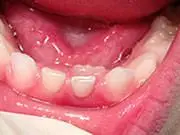

What to do if teeth are coming in behind baby teeth?

This is a very common occurrence with children, usually the result of a lower, primary (baby) tooth not falling out when the permanent tooth is coming in. In most cases if the child starts wiggling the baby tooth, it will usually fall out on its own within two months.

If it doesn't, then contact your pediatric dentist, where they can easily remove the tooth. The permanent tooth should then slide into the proper place.